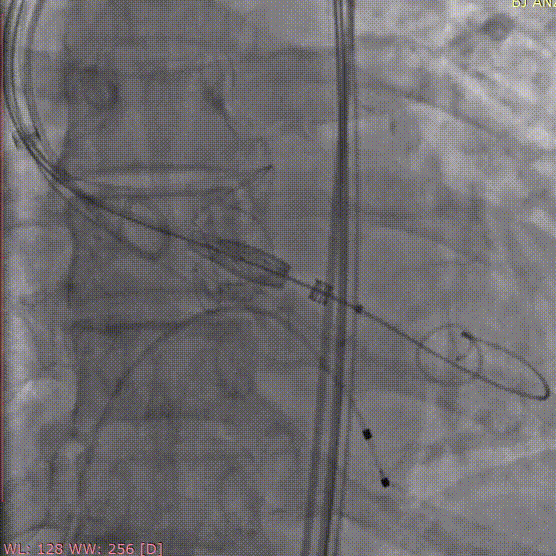

手术过程和结果

术中经股动脉切开建立血管通路,患者为单纯反流患者,无明显钙化,无需球囊预扩张,术中建立轨道后直接将输送器送入主动脉瓣目标位置,轻松实现定位件的正确入窦,后成功释放28mm瓣膜。经DSA造影和超声等综合评估显示瓣膜释放位置完美,瓣膜工作稳定,术后即刻主动脉瓣反流消失,人工主动脉瓣瓣环内无反流,无瓣周漏,患者临床症状和血流动力学明显改善。

术前造影

定位件入窦

释放瓣膜

术后造影